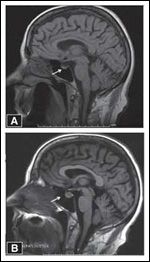

FIGURE 2

MRI Findings in a Patient With Ipilimumab-Induced Hypophysitis

Hypophysitis is the most commonly reported endocrine adverse reaction associated with ipilimumab.[14,18] Clinical manifestations of hypophysitis are probably dependent on the rapidity of onset, severity, and relative suppression of the endocrine axes (thyroid vs adrenal vs gonads). Enlargement of the pituitary gland on imaging of the brain has been reported as the earliest sign (Figure 2).[18] Abnormalities in laboratory testing and development of clinical symptoms of hormone deficiency usually follow the radiological changes.[18,48]

Symptoms of hormone deficiency vary and include fatigue, insomnia, loss of libido, anorexia, weight loss, severe hyponatremia, profound hypothyroidism, and/or symptoms mimicking Addison disease.[48-50] Hypophysitis resulting in enlargement of the pituitary gland can present with headache, nausea, vomiting, and/or visual disturbances.[48,50] The presentation can mimic that of bleeding or edema of intracranial metastasis and requires prompt evaluation. Hence, a high index of suspicion is required to diagnose hypophysitis, since signs and symptoms can be very subtle and misleading.